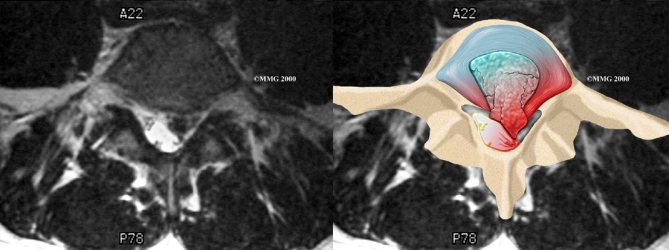

When more information is needed, your doctor may order magnetic resonance imaging (MRI). The MRI machine uses magnetic waves rather than X-rays to show the soft tissues of the body. It gives a clear picture of the discs and whether a herniation is present. Like the CT scan, this machine creates pictures that look like slices of the area your doctor is interested in. The test does not require special dye or a needle.

Magnetic Resonance Imaging (MRI)

Herniation occurs when the nucleus in the center of the disc pushes out of its normal space. The nucleus presses against the annulus, causing the disc to bulge outward. Sometimes the nucleus herniates completely through the annulus and squeezes out of the disc.

Herniation causes pain from a variety of sources. It can cause mechanical pain. This is pain that comes from the parts of the spine that move during activity, such as the discs and ligaments. Pain from inflammation occurs when the nucleus squeezes through the annulus. The nucleus normally does not come in contact with the body's blood supply. However, a tear in the annulus puts the nucleus at risk for contacting this blood supply. When the nucleus herniates into the torn annulus, the nucleus and blood supply meet, causing a reaction of the chemicals inside the nucleus. This produces inflammation and pain. A disc herniation may also put pressure against a spinal nerve. Pressure on an irritated or damaged nerve can produce pain that radiates along the nerve. This is called neurogenic pain.